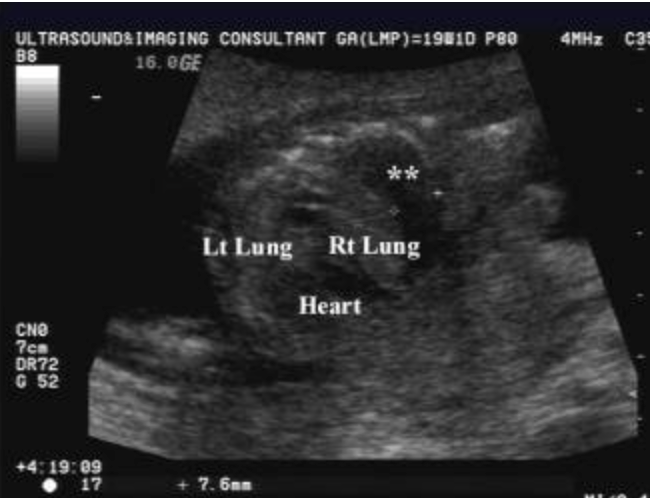

a) type 1 congenital cystic adenomatoid malformation

b) diaphragmatic hernia left side

c) diaphragmatic hernia right side

d) left lung agenesis